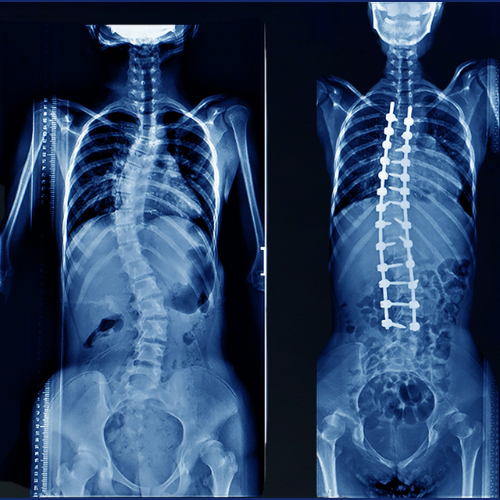

Scoliosis is an abnormal sideways curvature of the spine that can occur in children, adolescents, or even adults. Without timely treatment, scoliosis may leadRead More